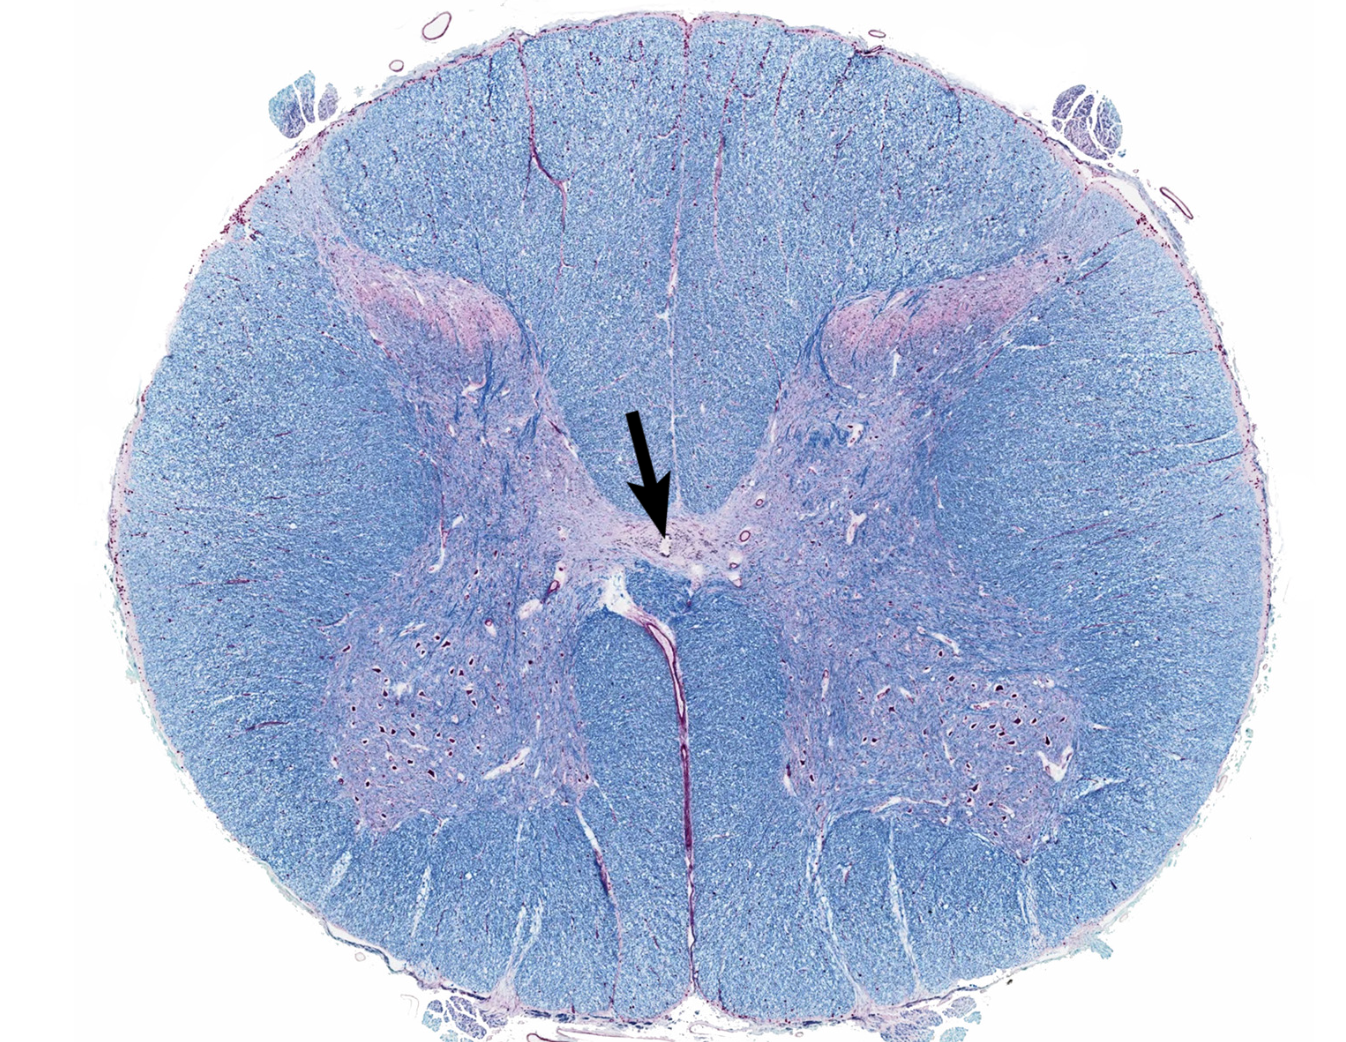

gray matter

posterior horn

anterior horn

lateral horn

gray commissure

central canal

white matter

posterior funiculus

anterior funiculus

lateral funiculus

posterior median sulcus

anterior median fissure